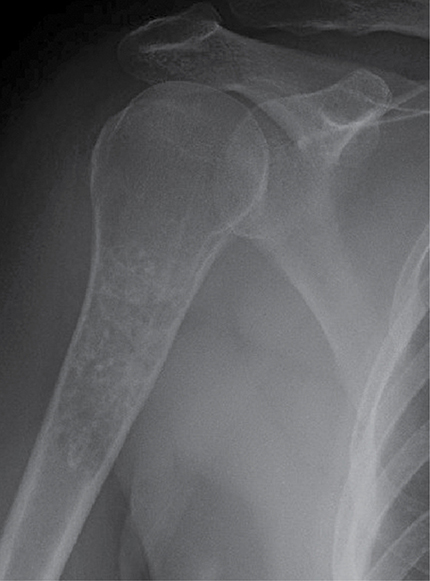

• Demystifying tumor classifications: key changes in bone and soft-tissue tumors

Cecilia Belzarena, MD, MPH, MBA

The latest edition of the “World Health Organization Classification of Tumors: Soft Tissue and Bone Tumors,” published in 2020, introduced several newly recognized soft-tissue and bone tumors.